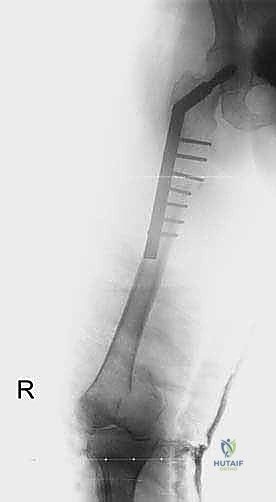

1. التثبيت الوقائي الداخلي (Prophylactic Internal Fixation)

إذا أظهرت الأشعة أن العظم ضعيف جداً وعلى وشك الانكسار، يقوم الدكتور هطيف بوضع أسياخ نخاعية معدنية (Intramedullary Nails) أو شرائح ومسامير متطورة داخل العظم لتدعيمه ومنع الكسر قبل حدوثه. هذه الجراحة الاستباقية توفر على المريض آلاماً مبرحة ومضاعفات خطيرة.

| جسم عظم الفخذ أو الساق | كسر مرضي كامل أثناء التحميل. | التثبيت بمسمار نخاعي تشابكي (Intramedullary Nailing). |

- الحالة الأولى: سيدة تبلغ من العمر 55 عاماً، متعافية من سرطان الثدي، عانت من ألم مبرح في الفخذ الأيمن وعجز كامل عن المشي بسبب كسر مرضي وشيك. بعد إجراء الفحوصات، قام الدكتور هطيف بإجراء جراحة تثبيت وقائي باستخدام مسمار نخاعي. في غضون 48 ساعة، استطاعت السيدة المشي بدون ألم، وعادت لممارسة حياتها وسط عائلتها.